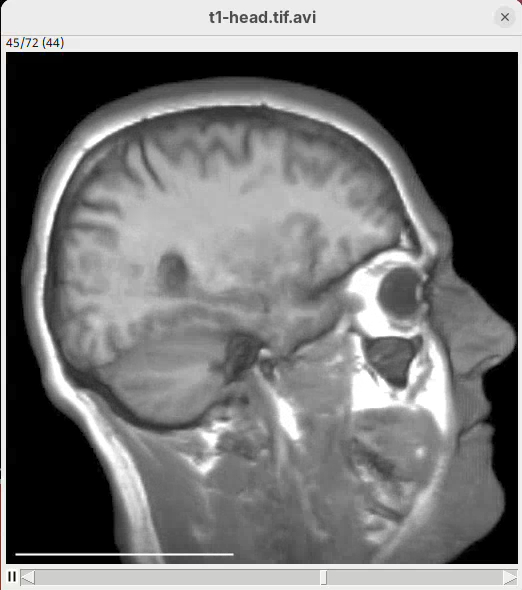

The BigDataViewer interface will open showing an optical section of the head sample.

Getting familiar with BigDataViewer is an essential skill for navigating large 3D datasets. It’ll also be important for the multiview registration pipeline. So, take the time to learn the basic commands and shortcuts. It is nicely intuitive. The BigDataViewer’s page on the ImageJ Docs has the official documentation and we can also go to Help > Show Help for an up-to-date overview.

Some of the movements to try:

Left-click and drag: turn the sample around the mouse pointer at any arbitrary angle.Right-click and drag: move the sample in the XY plane (of the view).Scroll: move through the Z plane (of the view). UseShift+Scrollto move fast.Ctrl+Shift+Scroll: zoom in or out.

But, most importantly, are the commands to put your sample back to its original orientation or along any of the original dimension axes:

Shift+Z: orient the sample on the XY plane.Shift+X: orient the sample on the ZY plane.Shift+Y: orient the sample on the ZX plane.

Finally, a visual tip. The default interpolation between image slices is nearest-neighbors. Press I to activate the tri-linear interpolation to obtain a much smoother (and improved) data visualization.